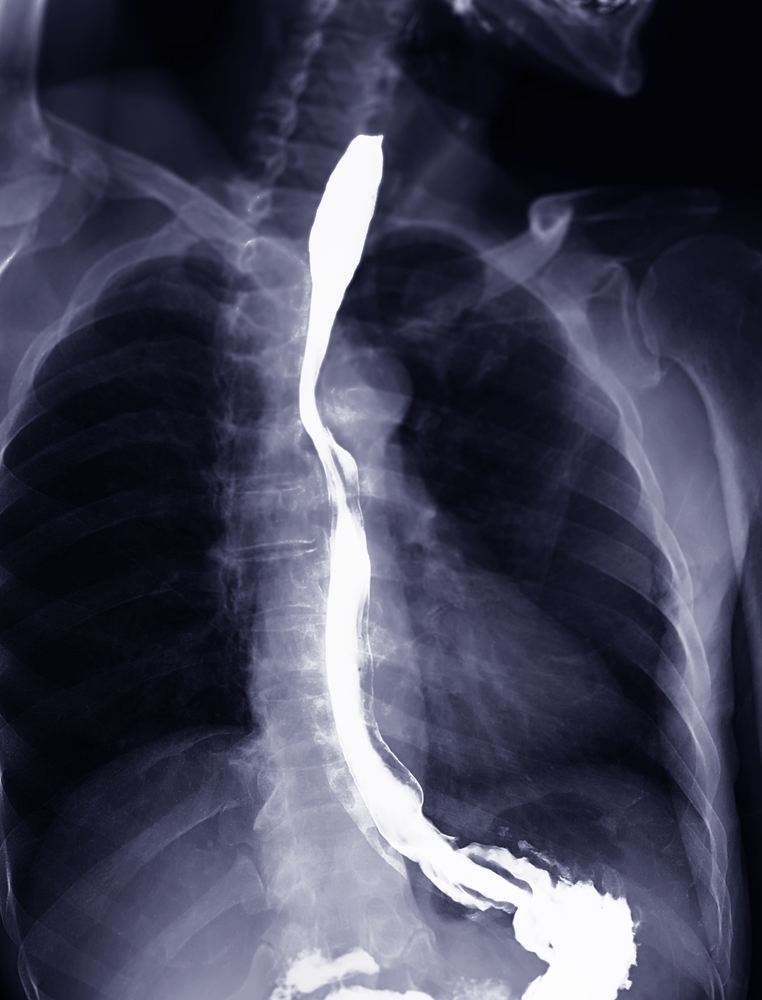

• Stemplės rentgenograma (bario testas): Atliekamas nuryjant specialų skystį ir stebint, kaip jis juda stemple. Taip galima aptikti tiek plėveles, tiek kitus susiaurėjimus.